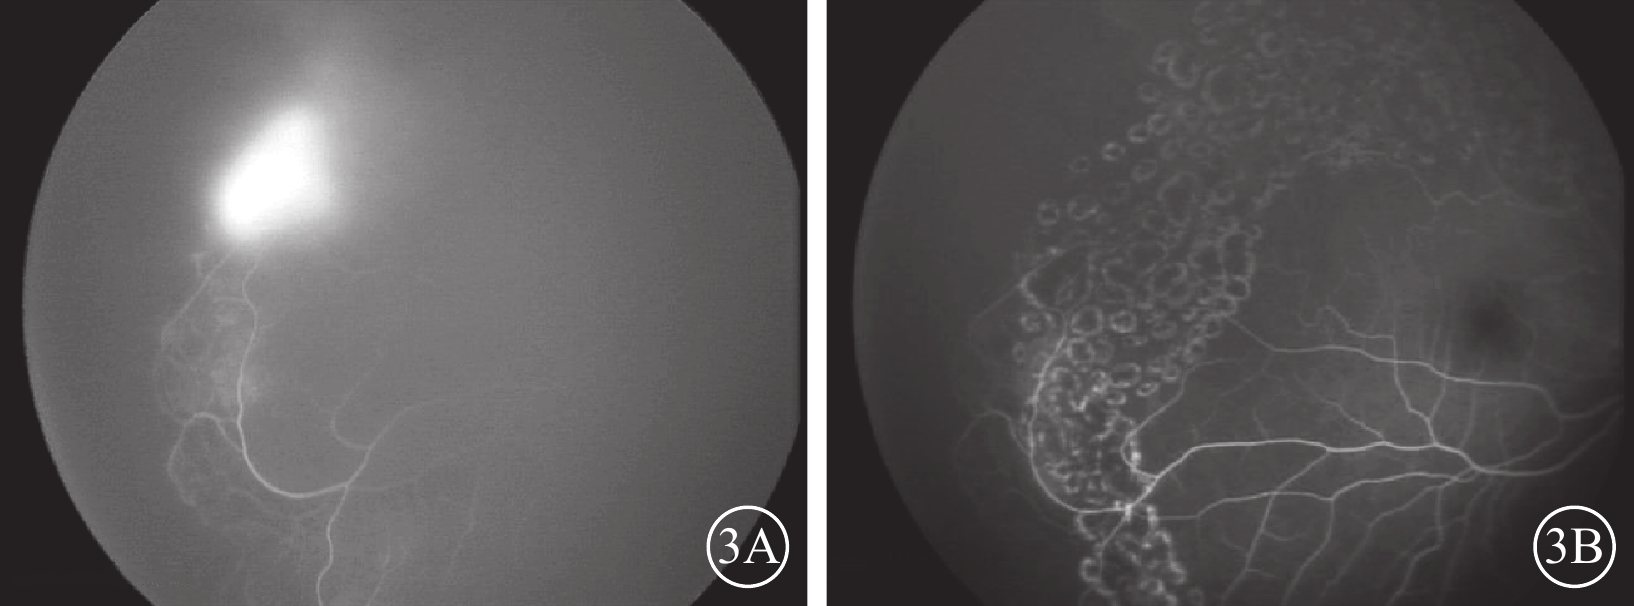

24只眼中,眼底有活動性病變7只眼(29.2%,7/24)。其中,視網膜周邊部新生血管6只眼;玻璃體積血合并高眼壓1只眼。行單純視網膜激光光凝治療2只眼,單次抗VEGF藥物治療1只眼,激光聯合抗VEGF藥物治療1只眼,PPV聯合激光光凝治療2只眼,預防性激光虹膜周邊切除1只眼。眼底無活動性病變17只眼。隨訪期間,眼底病變未進展23只眼。凡進行視網膜激光光凝治療者視網膜病變活動性有效控制(圖3),且隨訪期內無明顯進展;僅1只眼行單純抗VEGF藥物治療者復發視網膜視盤新生血管,再次行抗VEGF藥物治療,效果不佳,因患兒腦電圖提示癲癇,患兒家屬拒絕全身麻醉下行激光治療,末次隨訪時發展為玻璃體積血。